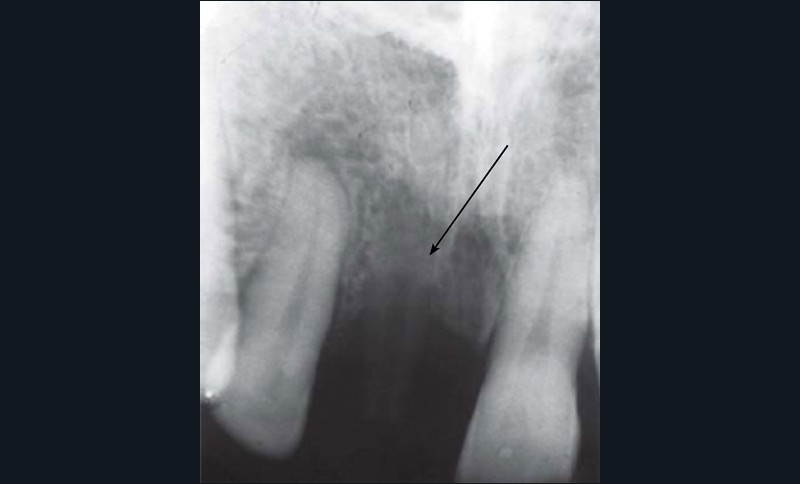

En termes de propriétés physiques, le PEEK présente de nombreux avantages. Sa densité et son module d’élasticité sont proches de ceux du tissu osseux. Il possède toutefois une limite de taille, puisqu’il est radio-transparent, ce qui complique considérablement l’analyse des clichés radiographiques pris en phase postopératoire (fig. 2) [5].